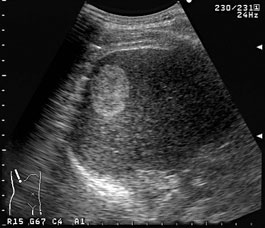

今回は肝臓の所見、肝血管腫についてお話ししようと思います。

肝血管腫は肝臓の良性腫瘍の中で最も頻度の高い腫瘍です。

細い血管がスポンジ状に集まったもので、多くはこのような高エコーの見た目をしています。

これは腹部エコーによって、必ずしも他の肝腫瘍と鑑別できるわけではないことに

注意が必要です。